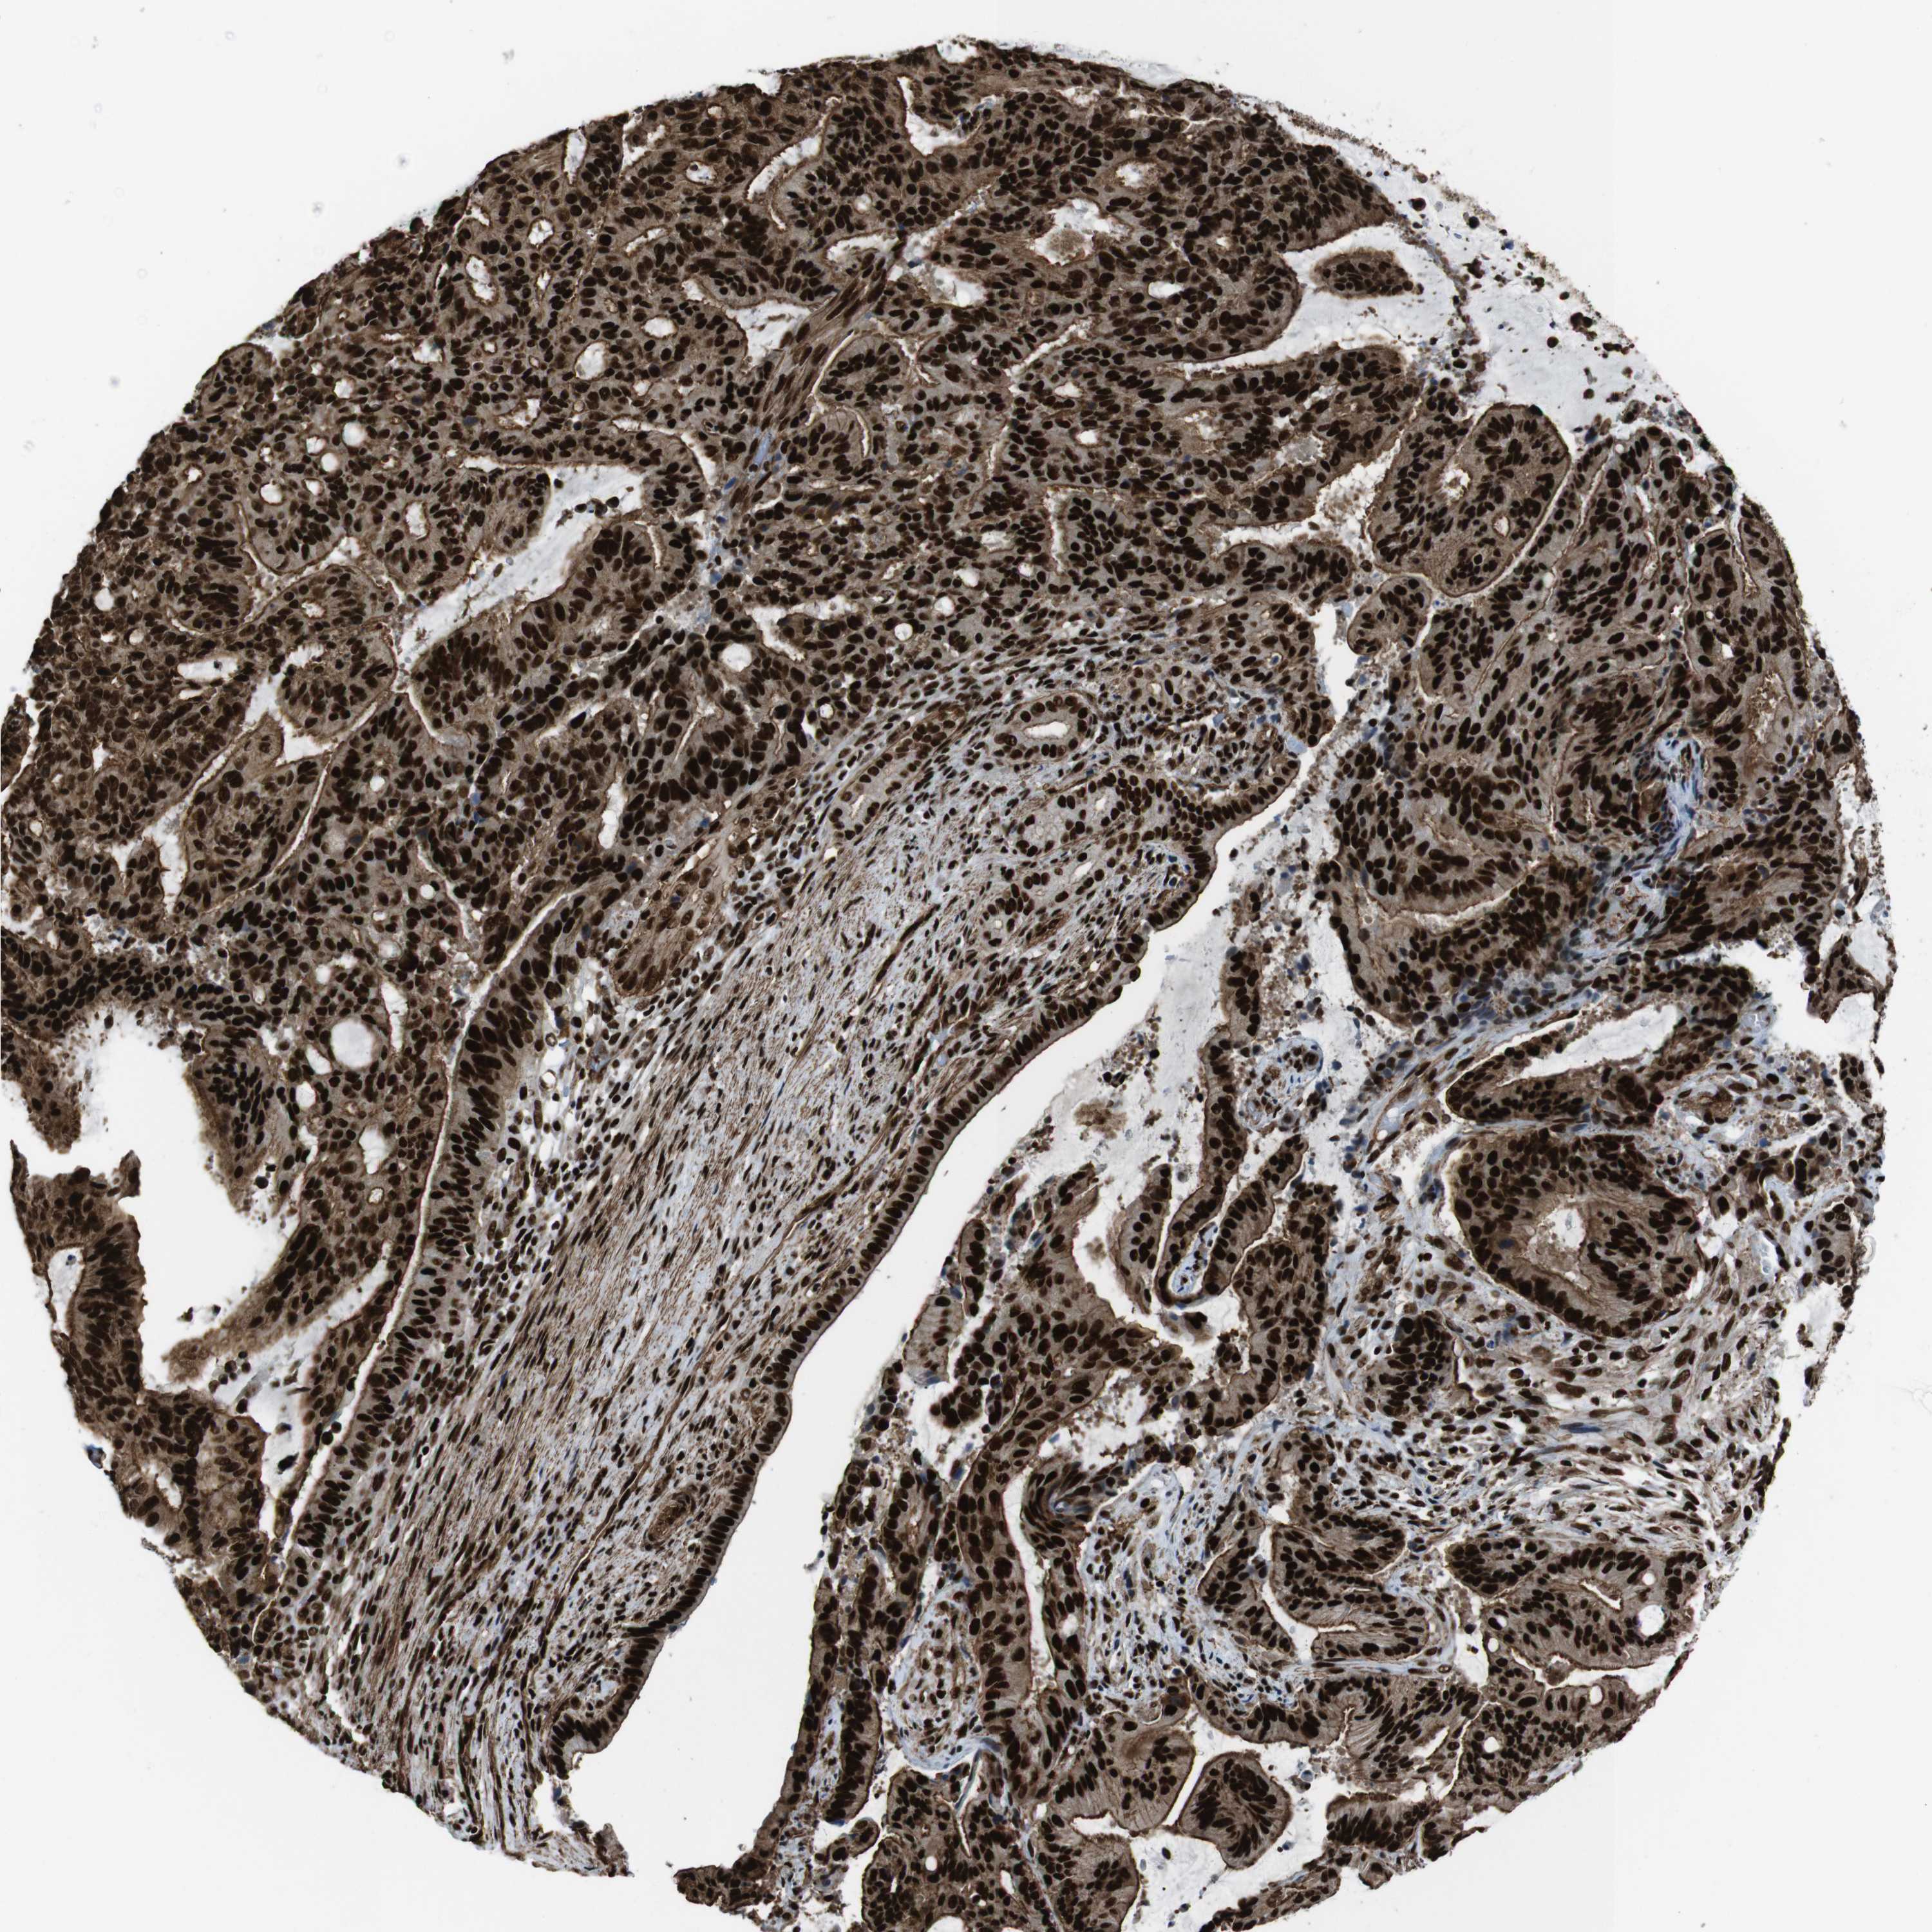

LIVER CANCER - Protein expressioni

A mouse-over function shows sample information and annotation data. Click on an image to view it in a full screen mode. Samples can be filtered based on level of antibody staining by selecting one or several of the following categories: high, medium, low and not detected. The assay and annotation is described here.

Antibody stainingi

Antibody staining in the annotated cell types in the current human tissue is reported as not detected, low, medium, or high, based on conventional immunohistochemistry profiling in selected tissues. This score is based on the combination of the staining intensity and fraction of stained cells.

Each image is clickable and will lead to virtual microscopy that enables deeper exploration of all samples and also displays staining intensity scores, fraction scores and subcellular localization as well as patient and tissue information for each sample.

Antibody HPA041057

Antibody HPA058707

Antibody CAB011532

Staining

High

Medium

Low

Not detected

Intensity

Strong

Moderate

Weak

Negative

Quantity

>75%

75%-25%

<25%

None

Location

Nuclear

Cytoplasmic/membranous

Cytoplasmic/membranous,nuclear

Cholangiocarcinoma

Carcinoma, Hepatocellular, NOS